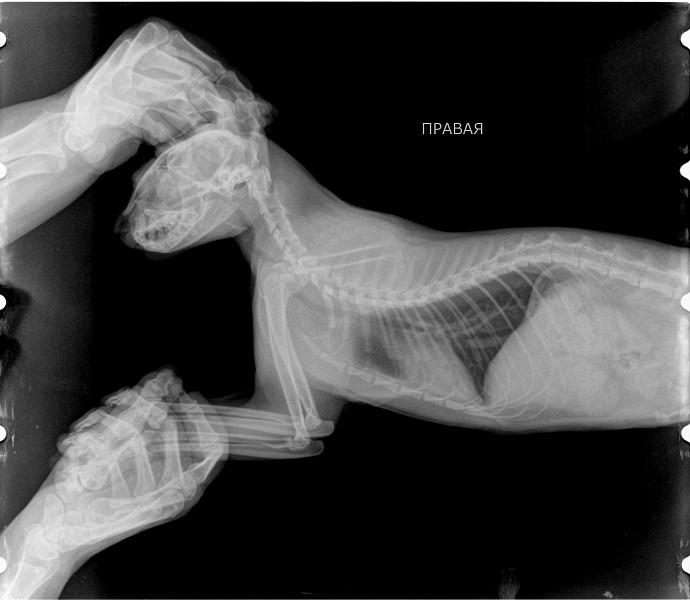

Рентгеновские снимки головы кошки в боковой проекции